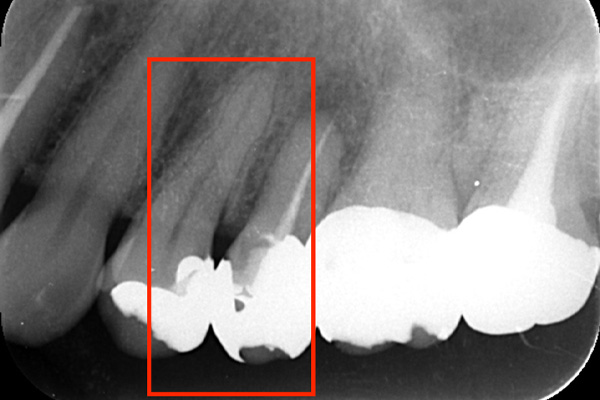

根の先端に膿が溜まっています。

根の中の白い縦の線がなくなっています。これは、中に詰まっていた、防腐剤を取り除いた証拠になります。取り除いてから、根の中をしっかり清掃していきます。

清掃が終わり、患者様も違和感がなくなったということで、防腐剤を再び詰めていきました。最初に入っていたものと比較して緊密に太く入っているのがわかります。

6ヶ月後。根の先端に溜まっていた膿(黒い影)がなくなっています。なくなったことが確認できてから、かぶせ物をかぶせていきます。

根の中に入っていた防腐剤を取り除いた時の写真です。感染物質が付着して黒くなっているのがわかります。

また、防腐剤をとりのぞけても、その防腐剤を歯の根のなかにくっつける素材が残っていますので、それもしっかり取り除きます。

目ではなかなか全てを見ることができないので、右の写真の様にマイクロスコープをもちいて拡大してみていきます。